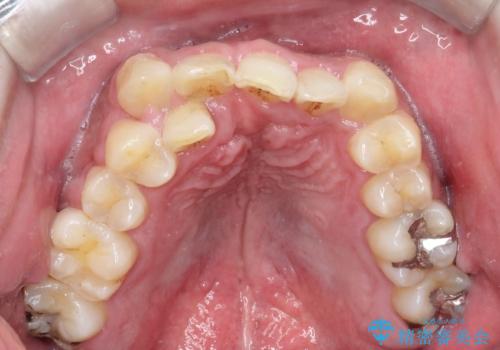

- 主訴:噛み合わせが反対になっているのを治したい

反対咬合と叢生改善のため、上下左右4番目の歯を抜歯し、審美装置にて矯正治療を行いました。

骨格性Ⅲ級を示しましたが、構成咬合位がとれたことから反対咬合と叢生改善のため、上下左右第一小臼歯を抜歯しワイヤー矯正を行いました。途中、バイトアップを行っています。